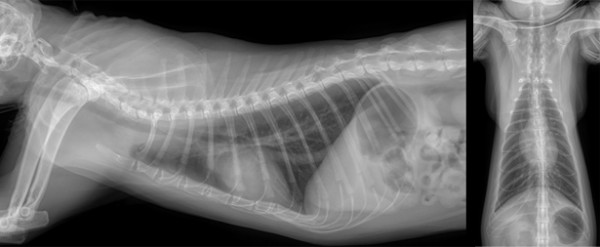

- 영상 및 심장 혈액 검사 -

흉부 방사선(VHS 7.3) 과 심장 키트(proBNP 50) 결과,

기침의 원인이 심장 질환일 가능성은 배제되었습니다.